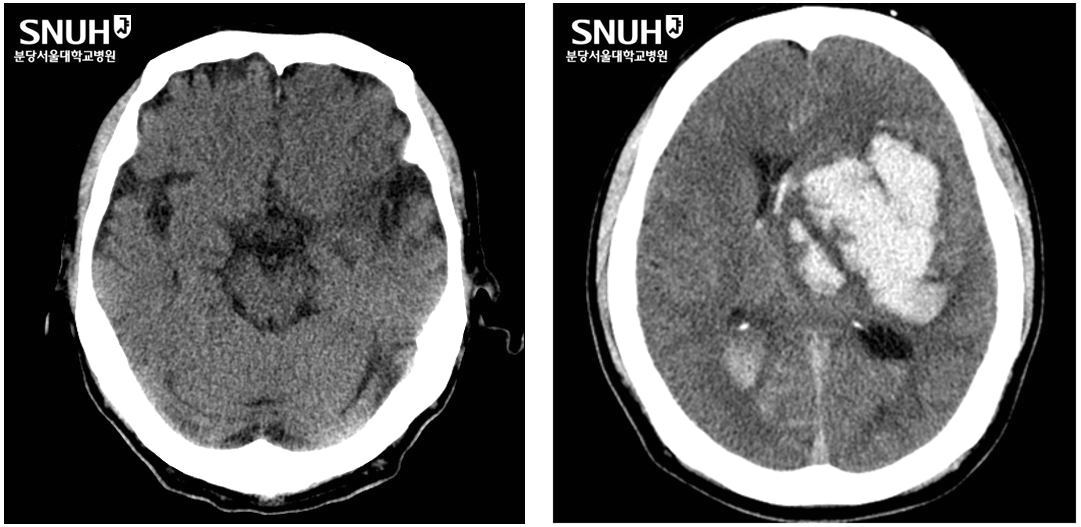

[생생 건강정보] 韓 사망원인 3위 '뇌출혈'…극심한 두통으로 시작